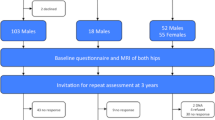

We performed a case-control study comparing a group of elite basketball athletes with a group of age-matched nonathletes (Table 1). All volunteers in both groups were included in a previous publication [18]. Volunteers had been recruited by written invitation and without reimbursement. In the previous study, we excluded patients with known hip disease, including hip dysplasia, Perthes disease, slipped capital epiphysis, or previous severe hip trauma or hip surgery. The 37 (74 hips) athletes were recruited during a 1-year period from an elite basketball club playing in the national league of Germany. The age-matched control group of 38 (76 hips) volunteers was recruited from middle, high, and medical schools in Bern, Switzerland. All volunteers were Caucasians with European nationalities. Exclusion criteria also applied in the previous study, for one (previous surgery) of the original 38 athletes and for two (too high sports level) of the original 40 less sports-active volunteers. MRI was performed on both hips in volunteers resulting in 74 MRI scans of the athletes (two MRI scans deleted for poor quality) and 76 MRI scans in the volunteer group. The age limit of 26 years in the previous study was reduced to 22 years in the current study to obtain optimal reading of the physeal scar on the MRI scans. This left 55 hip MRI scans for the athletes and 60 hip scans for the control group. Six of the original 55 MRI scans of the athletes’ hips and seven of the 60 MRI scans of the control subjects also were excluded because their physis, or physeal scar, could not be adequately seen on MRI (Table 1). Reasons for inadequate physeal observation included excessive motion artifact and normal disappearance of the physeal scar with aging. In each of the two groups, hip MRI scans were stratified into those with open physes and those with closed physes based on the radiographic appearance of the capital femoral physis on MRI (Table 1). Our hospital ethical committee approved the study and each participant gave written consent. Parent consent, in additional to personal consent, was obtained for all participants younger than 18 years.